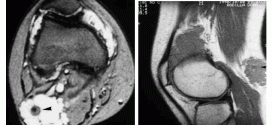

CONDROSARCOMA

El condrosarcoma. Es un tipo de cáncer Se forma en las células de los cartílagos del cuerpo. El cartílago es el tejido conjuntivo. La mayoría de los huesos son formados a partir del cartílago. Se halla en varias áreas del cuerpo. El cartílago es básicamente el tejido resistente elástico que forma una cubierta protectora sobre los extremos de los huesos. …